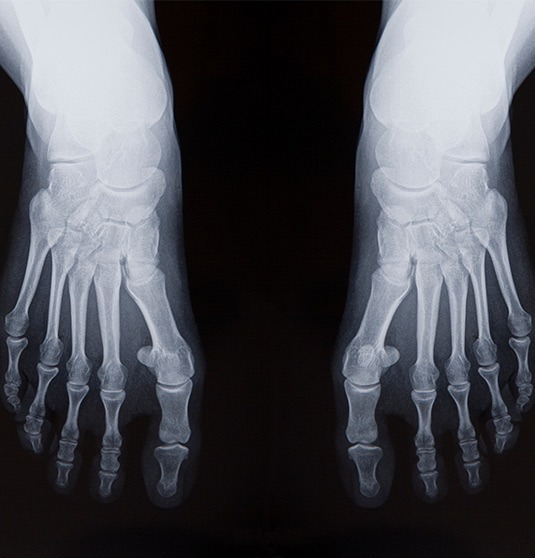

Splay Foot is challenging to live with, to say the least! The condition can affect one or both feet and often leads to various issues and symptoms that can interfere with daily activity and quality of life.

Those who suffer from Splay Foot will notice a reduction in their quality of life due to the pain and discomfort caused. If not treated, the whole body can become impaired due to the wrongly positioned placement of the foot.